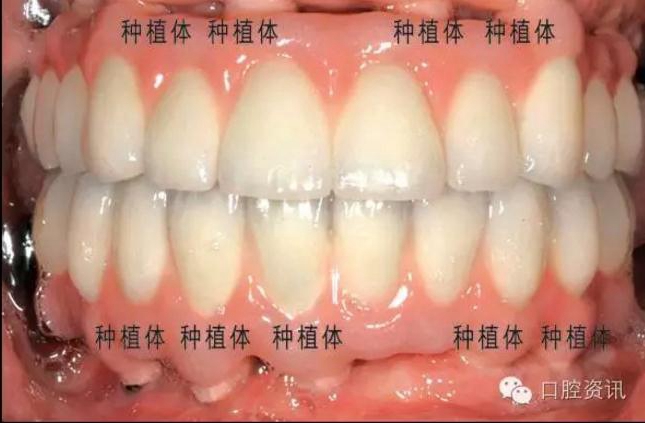

8. 種植牙和真牙看上去一模一樣嗎?

種植牙義齒可以代替單顆牙齒、連續(xù)多顆牙齒或者整排牙齒。正確的

植入和修復會使種植牙呈現(xiàn)令人滿意的美觀效果。目前, 先進的臨床

技術(shù)和材料已經(jīng)可以讓種植牙修復達到令人滿意的美學效果。一般情

況下,是看不出來種植牙和真牙的區(qū)別的,真假難辨。

17.jpg

圖 17. 種植牙修復單顆前牙缺失

18.jpg

圖18. 種植牙修復上下頜全口牙缺失